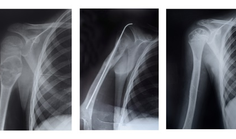

_ OsteoporosisWhy an Osteoporosis Drug Works By Sondra Forsyth articleRaloxifene is a U.S. Food and Drug Administration (FDA)-approved treatment for decreasing fracture risk in osteoporosis. While raloxifene is as effective at reducing fracture risk as other current treatments, the medication works only partially by suppressing bone loss. With the use of wide- and small-angle x-ray scattering (WAXS and SAXS, respectively), researchers carried out experiments at the U.S.